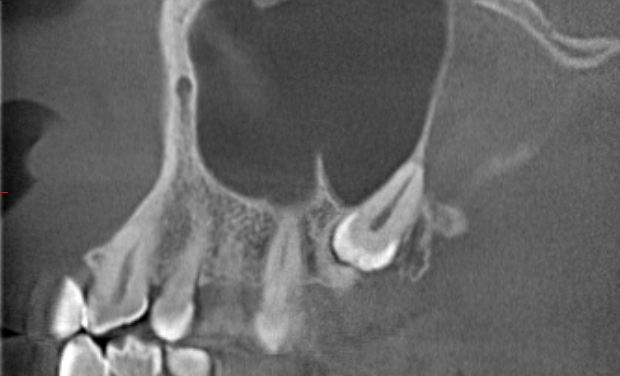

CBCT具有扫描速度快,空间分辨率高,辐射剂量小,图像伪影小等优点,其对颌面、牙齿、骨骼的良好成像效果,高质量的三维立体图像,图像精度提高,无几何失真,可以进行清晰的实际测量。此外,放射剂量更小,尽管高于普通平片,但由于能够满足传统检查无法实现的诊断需求,因此,被广泛用于口腔科临床诊断和治疗,有助于临床做出精确诊断及临床治疗计划的制定与实施。适应症分别有:正畸:三维头影测量、气道分析、正畸种植支抗定位。修复种植:评估患者的骨质、骨量、并掌握下颌神经管、鼻底上颌窦等重要的位置,可以方便设计和制作手术导板。牙体牙髓:疑难根管、遗漏根管及钙化根管的影像诊断。牙周:牙周病的评估。口腔颌面外科:埋伏牙、阻生牙、多生牙的三维定位、颌面部骨折、颞下颌关节紊乱的诊断。

(可以通过CBCT观察牙齿与颌骨、下牙槽神经管、上颌窦的位置关系)